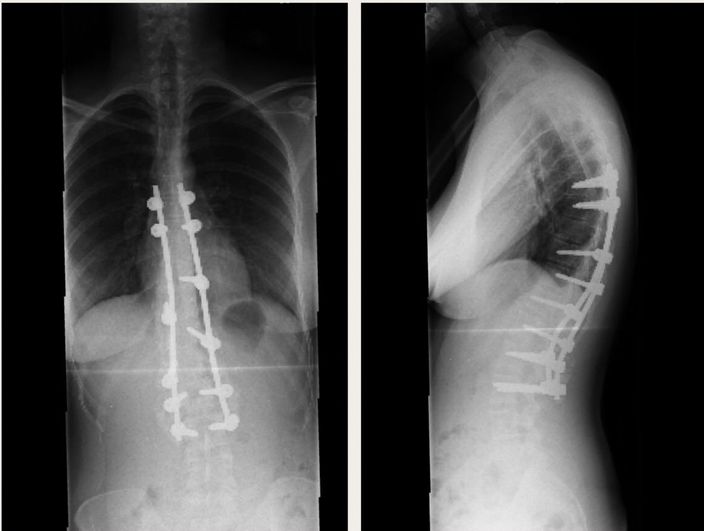

「脊椎側彎矯正」手術要在脊椎骨上鎖上鋼釘、鋼鈎,把上下的骨頭用外力拉直。如果側彎嚴重,還要從身體正面對韌帶、椎間盤、軟骨放入拉力支架,這倘手術絕對是大手術。女網民告誡,日常長期不正確的姿勢會造成脊椎彎曲,特別是長時間坐姿不對最容易令脊椎歪掉,翹腳就是一大有害的動作。